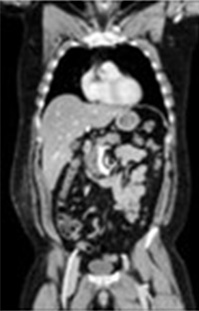

CT検査室

体の周囲360度からX線を照射し、体内を透過したX線量を解析し、画像にします。輪切りの画像だけでなく任意の断面の画像を作成でき、血管や骨などを立体的(3D)に表示することができます。 撮影時間を短縮、広範囲を撮影でき、息止めがある検査でも数秒と負担なく検査を受けられます。また体の大きさ、形に合わせてX線の量が自動で調整されるため被ばくを低減することができます。